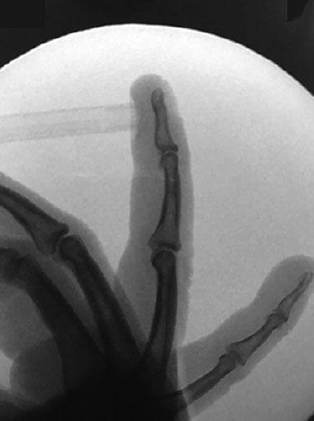

An 18-year-old female gymnast comes to the office because of the sudden onset of pain, swelling, and ecchymosis of the right ring finger that began 3 days ago while she was practicing hand-only climbing on a rock-wall. Physical examination shows tenderness over the palmar aspect of the finger at the proximal phalanx. Isolated flexion at the distal interphalangeal joint and flexion of the digit at the proximal interphalangeal joint while the remaining digits are held in hyperextension are intact. The patient can fully flex and extend the finger, and the proximal interphalangeal joint is stable to stress. X-ray study is shown. Which of the following is the most likely cause of the findings in this patient?

The correct response is Option C.

An injury originally identified in rock climbers, rupture of the A2 pulley has been increasingly recognized in other sports and activities. The forceful flexion of the flexor profundus and superficialis tendons with the PIP joint flexed 90 degrees and the distal interphalangeal (DIP) joint extended (the “crimp” position) placed loads exceeding the tolerance of the A2 across the palmar PIP joint, resulting in rupture of the underlying pulley. Treatment for an isolated pulley injury includes rest, ice, anti-inflammatory drugs, and external support through use of a ring splint.